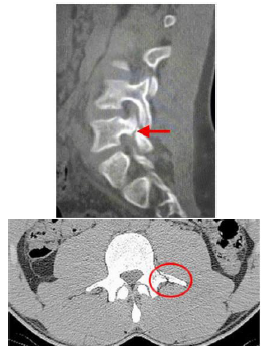

Durante a copa do mundo de 2014, um jogador de futebol recebeu uma falta e, após o lance, não conseguiu retornar à partida em virtude de forte dor lombar. Foi, então, levado ao hospital, onde foi realizada a seguinte imagem:

Sobre o quadro, considerando a imagem, é correto afirmar que